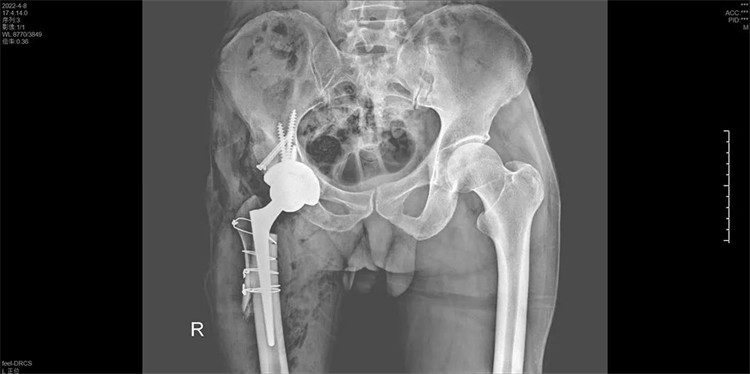

羅軍主任組織科室多次討論,并及時與患者及家屬溝通,決定依靠先進的3D打印技術(shù),為患者進行術(shù)前規(guī)劃,精準(zhǔn)定位真臼,恢復(fù)雙下肢的長度,量身定制進行精準(zhǔn)手術(shù)治療方案根據(jù)CT數(shù)據(jù)打印出3D模型,實現(xiàn)精準(zhǔn)置換。

羅軍主任首先為周大伯進行了CT掃描,將周大伯雙髖關(guān)節(jié)CT掃描數(shù)據(jù)傳輸?shù)?D打印機,按照1:1的比例用3D技術(shù)“打印”了一個一模一樣的髖關(guān)節(jié)模型。該模型將周大伯的壞死關(guān)節(jié)及脫位程度和其他細(xì)節(jié)完美呈現(xiàn)。借助該模型,羅主任能“直觀”周大伯骨骼病變的三維立體結(jié)構(gòu),除了有助于制定詳細(xì)的手術(shù)預(yù)案外,還能利用模型進行術(shù)前模擬截骨、固定,選擇好合適的人工髖關(guān)節(jié)假體及3D打印補塊,提前預(yù)演整個手術(shù)過程,預(yù)見復(fù)雜手術(shù)過程中可能出現(xiàn)的各類難題,從而提高了手術(shù)的精準(zhǔn)率,并大幅縮短了手術(shù)時間,更降低了手術(shù)風(fēng)險、減少并發(fā)癥出現(xiàn)。

手術(shù)過程一氣呵成,手術(shù)歷時2個小時,出血200ML,順利地為周大伯進行了右側(cè)人工全髖關(guān)節(jié)置換術(shù),將人工髖關(guān)節(jié)準(zhǔn)確地安裝在周大伯的真臼內(nèi)并做了牢固的固定。術(shù)后第1天周大伯就已下地行走。